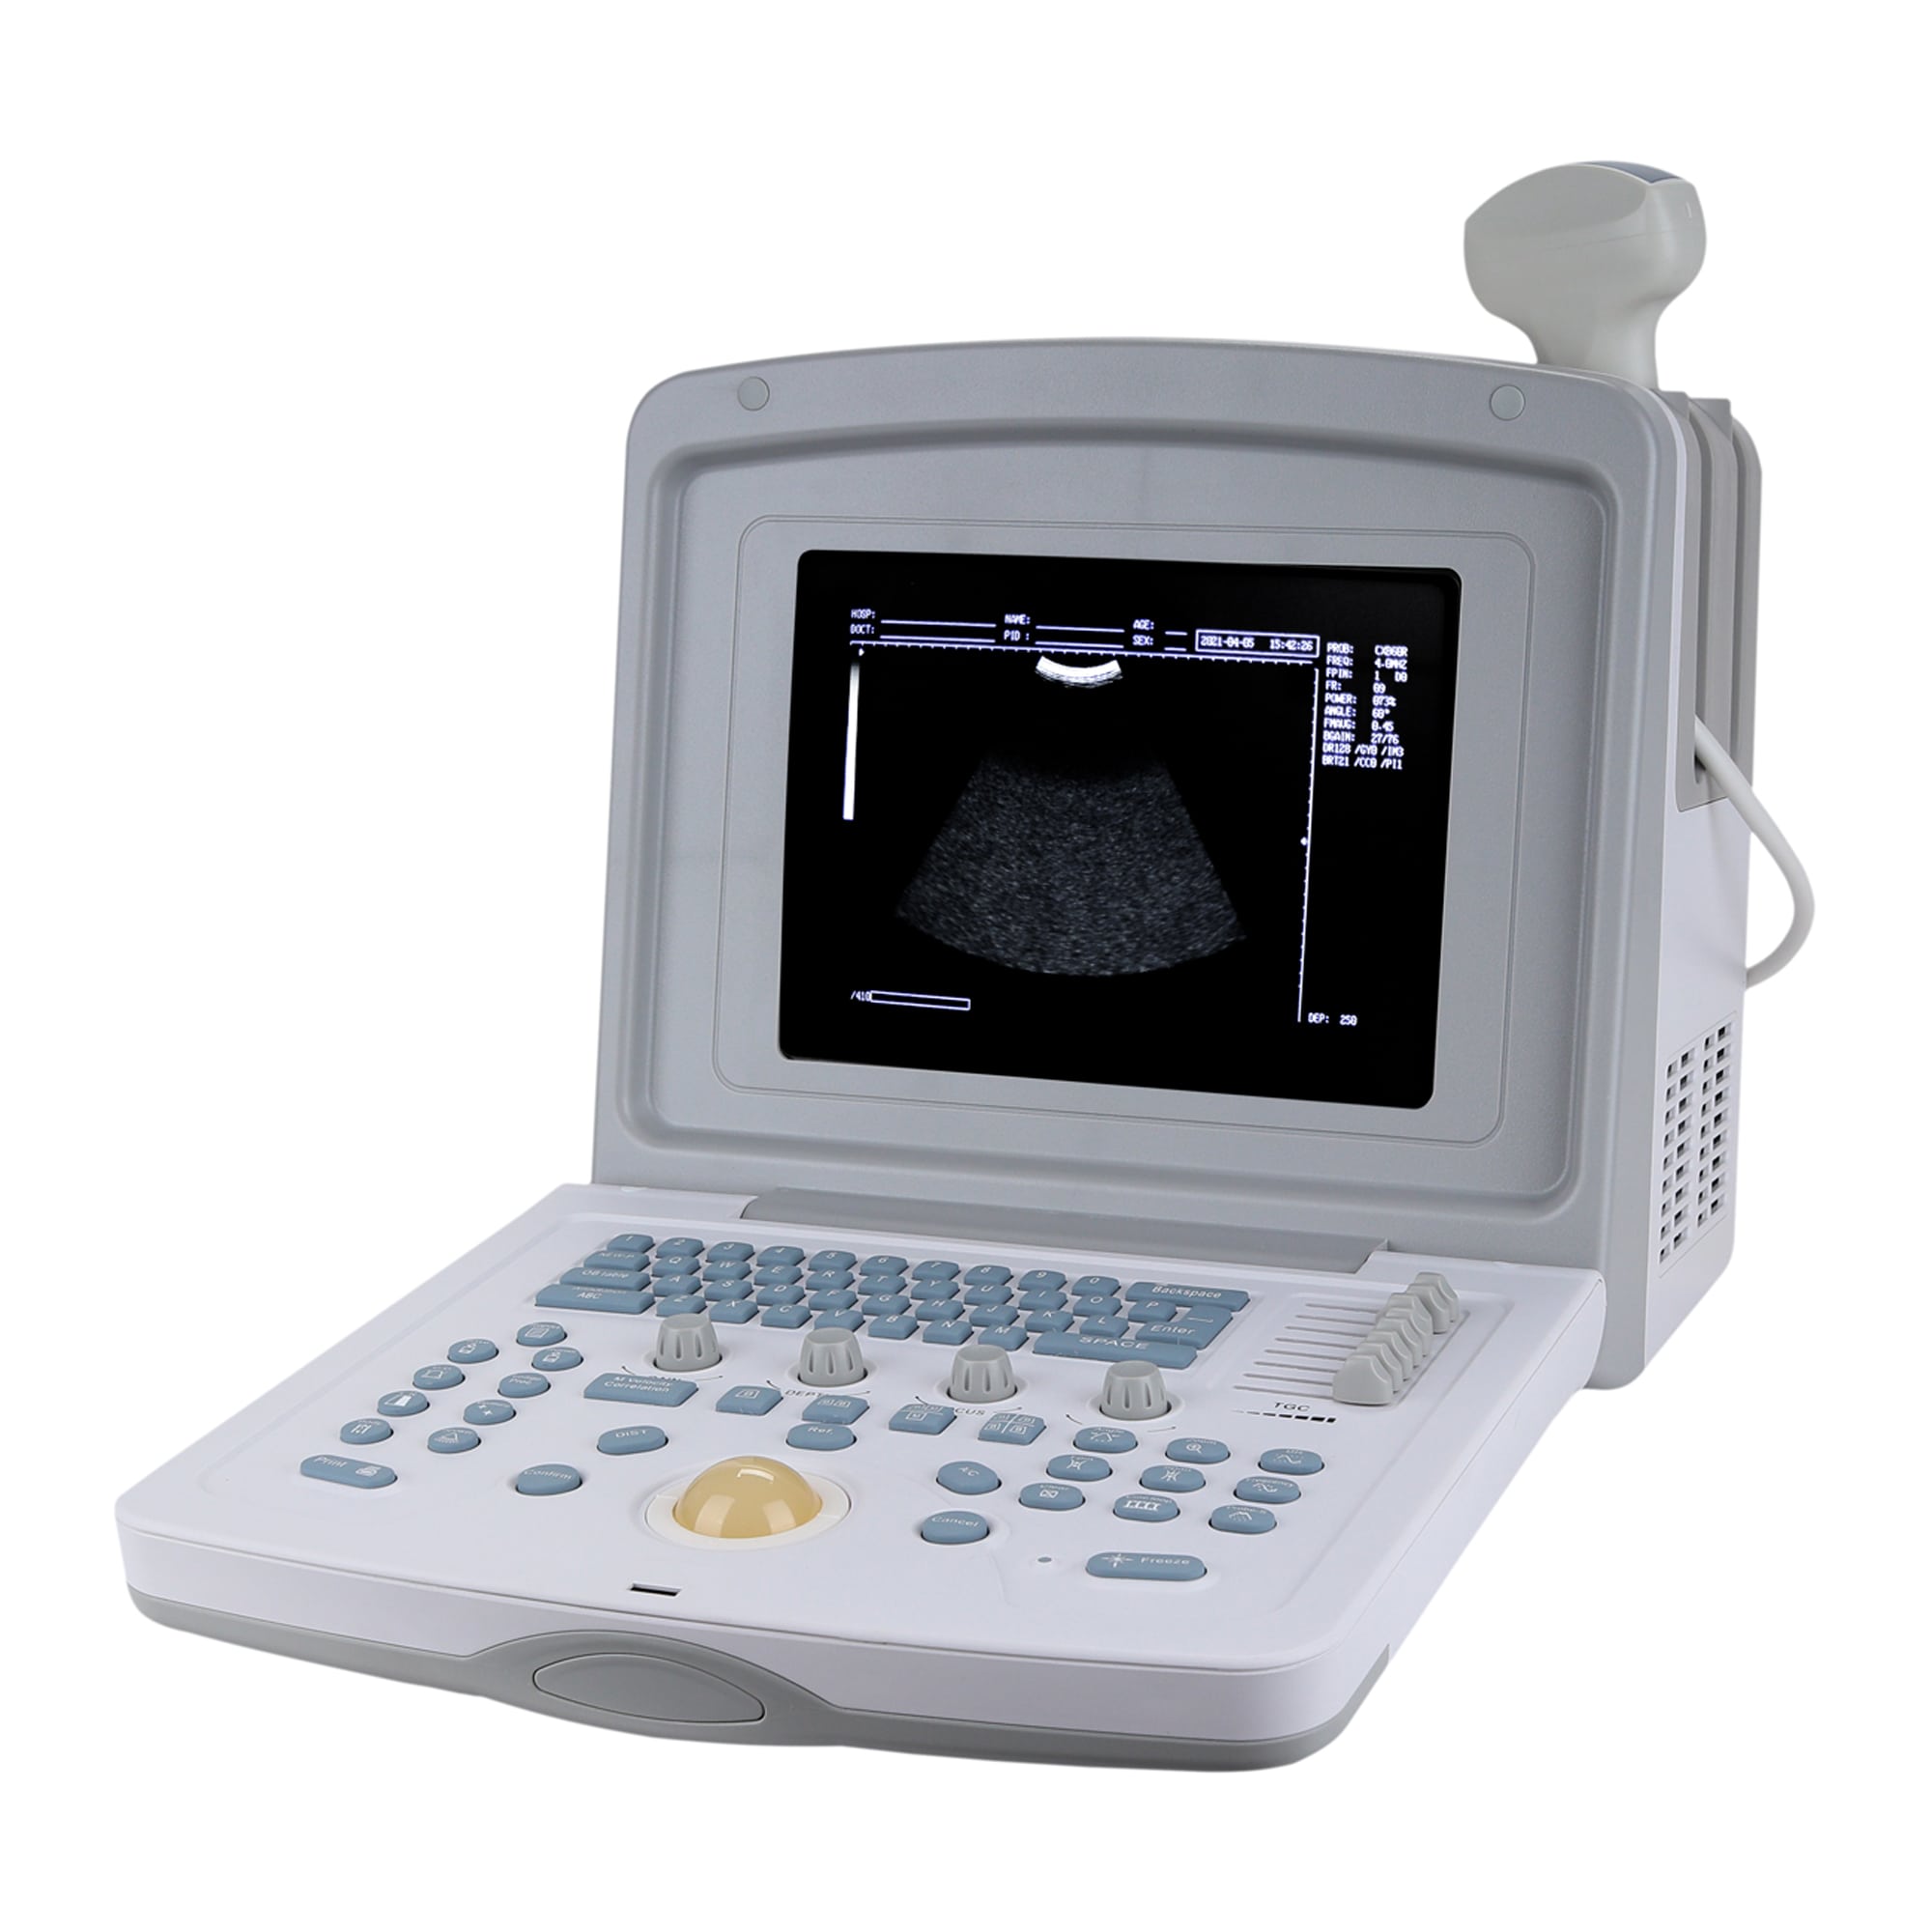

УЗИ аппараты российского производства: обзор и характеристики